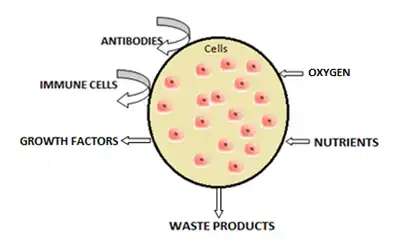

Cell encapsulation is a possible solution to graft rejection in tissue engineering applications. Cell microencapsulation technology involves immobilization of cells within a polymeric semi-permeable membrane. It permits the bidirectional diffusion of molecules such as the influx of oxygen, nutrients, growth factors etc. essential for cell metabolism and the outward diffusion of waste products and therapeutic proteins. At the same time, the semi-permeable nature of the membrane prevents immune cells and antibodies from destroying the encapsulated cells, regarding them as foreign invaders. On the other hand, single-cell nanoencapsulation (SCNE) involves the formation of nanometric shells around individual living cells.[1]

Microcapsule permeability

A fundamental criterion that must be established while developing any device with a semi-permeable membrane is to adjust the permeability of the device in terms of entry and exit of molecules.[55][56] It is essential that the cell microcapsule is designed with uniform thickness and should have a control over both the rate of molecules entering the capsule necessary for cell viability and the rate of therapeutic products and waste material exiting the capsule membrane. Immunoprotection of the loaded cell is the key issue that must be kept in mind while working on the permeability of the encapsulation membrane as not only immune cells but also antibodies and cytokines should be prevented entry into the microcapsule which in fact depends on the pore size of the biomembrane.[56]